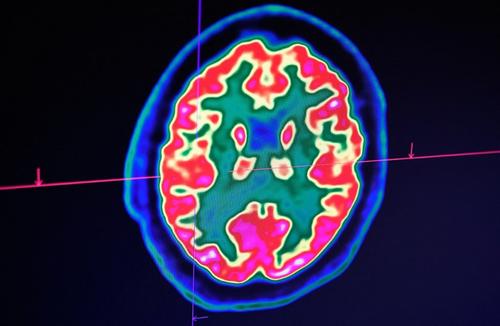

Une mystérieuse maladie du cerveau inquiète au Canada

Au Canada, les autorités sanitaires de la province du Nouveau-Brunswick enquêtent sur une mystérieuse maladie neurologique, détectée à ce jour chez une quarantaine de personnes. >>>

Voici comment communiquent les cellules cérébrales